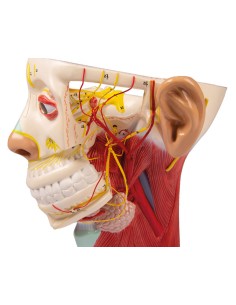

Scopri il Mondo dell’Anatomia con Modelli anatomici di Precisione

Modelli Anatomici Dettagliati per Ogni Necessità

Dal cranio in 22 parti con incastri magnetici ai modelli di colonna vertebrale, da quelli di articolazioni a quelli di cuore, ogni pezzo della nostra collezione è progettato per un’immersione totale nello studio dell’anatomia umana. I nostri modelli, realizzati tramite scansioni di ossa vere, garantiscono un’esperienza tattile autentica e una fedeltà di peso quasi identica agli originali.

Strumenti Didattici Innovativi per l’Educazione e la Pratica Medica

Essenziali per studenti e professionisti, i nostri modelli anatomici sono strumenti didattici che permettono di osservare le strutture anatomiche con precisione, eliminando la necessità di dissezioni o studi invasivi. Sono inoltre utili per spiegare ai pazienti le patologie, rendendo la comunicazione più efficace e risparmiando tempo prezioso.